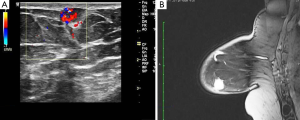

Mammography showed a relatively well-defined mass with sparse calcifications (Figure 1A), whereas ultrasonography revealed a circumscribed microlobulated hypoechoic mass measuring 1cm without posterior acoustic enhancement (Figure 1B). On color Doppler examination the mass exhibited marked hypervascularity (Figure 2A). A breast magnetic resonance imaging (MRI) was obtained and demonstrated a nodule measuring 1cm with partially irregular margins located 9 cm from the nipple in the lower inner quadrant of the right breast (Figure 2B). After contrast administration a rapid increase of the signal intensity was noted followed by a wash out curve in the delayed phase and thus the lesion was classified as BIRADS category 5. Cytology examination was not performed because a repeated aspiration of the nodule yielded only blood.

On ultrasonography, breast hemangioma may have a variable appearance. It most commonly appears as a superficially located oval mass with parallel orientation and circumscribed margins. Internal echostructure is variable and the tumor can be hypoechoic, isoechoic or hyperechoic (1,3-5,11). Compressibility of the tumor may be detected only in the absence of thrombosis (7). In some cases an isoechoic tumor cannot be clearly displayed from the surrounding adipose tissue (5). Although the vascularity of the tumor has not been reported to have diagnostic value (2), the presence of hypervascularity may indicate a suspicious of malignancy tumor (7).

There are only a few reports of MRI features of breast hemangioma (9,12,16,18). The tumor appears as an ovoid mass that is isointense to surrounding fibroglandular tissue on T1-weighted images and hyperintense on T2-weighted images (12). Early enhancement following contrast administration may indicate a suspicious lesion (3). However, the MRI findings are variable depending on the possibility of internal thrombosis (1).